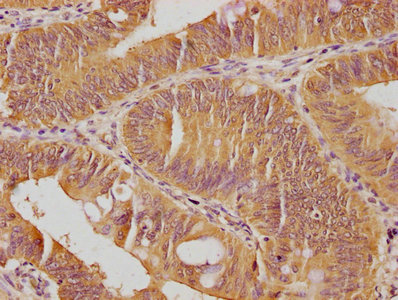

IHC image of CSB-PA009018PA01HU diluted at 1:100 and staining in paraffin-embedded human colon cancer performed on a Leica BondTM system. After dewaxing and hydration, antigen retrieval was mediated by high pressure in a citrate buffer (pH 6.0). Section was blocked with 10% normal goat serum 30min at RT. Then primary antibody (1% BSA) was incubated at 4°C overnight. The primary is detected by a biotinylated secondary antibody and visualized using an HRP conjugated SP system.